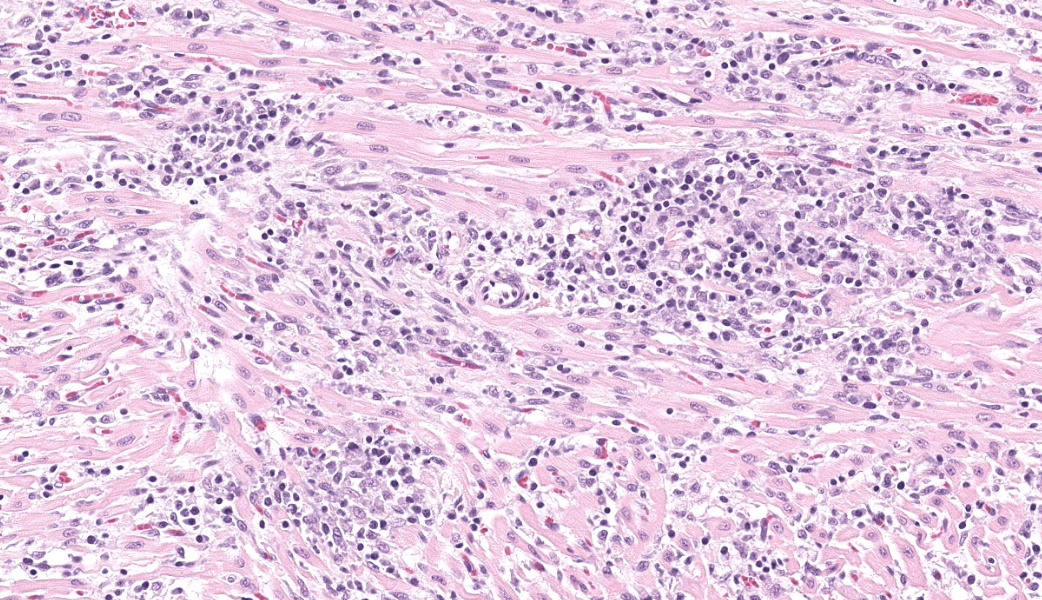

Expanding and infiltrating all layers of the heart, with the greatest severity in the myocardium, are large numbers of plasma cells, lymphocytes, and macrophages. Cardiomyocytes in areas of inflammation are multifocally hypereosinophilic, shrunken, and have striation loss with fragmented to absent nuclei (necrosis). There is mild, multifocal, interstitial fibrosis often associated with cardiomyocyte degeneration and inflammation. Throughout the myocardium, there are occasional cardiomyocytes that contain intrasarcoplasmic, variably sized (up to 100 μm in length) pseudocysts with numerous, 2-3 μm, round protozoal amastigotes.Contributor's Morphologic Diagnoses:

Heart: Severe, multifocal, chronic-active, lymphoplasmacytic and histiocytic pancarditis with intrasarcoplasmic pseudocysts containing amastigotesContributor's Comment:

T. cruzi can infect myocytes, endothelial cells, fibroblasts, and adipocytes, but has a tropism for cardiac muscle tissue.11 Grossly, there are no pathognomonic lesions for Chagas disease. Histologically, the cardiomyocytes will be expanded by a pseudocyst containing amastigotes. While best observed ultramicroscopically, the amastigotes will have a large nucleus and an adjacent rod-shaped kinetoplast, like Leishmania spp. Unlike the defined perpendicular orientation of the kinetoplast in Leishmania, the location of the kinetoplast relative to the nucleus changes during the life cycle and cannot be a diagnostic feature in Chagas disease.10 Unfortunately, additional diagnostics including PCR, culture, and serology were not performed so leishmaniasis cannot be completely ruled out, but the geographic and anatomic location of the organism along with the histologic appearance is most likely consistent with T. cruzi. Infection results in marked inflammation of the heart, often not associated with the intracellular pseudocysts. Myocarditis can lead to heart failure with cardiac arrest and potentially fatal arrhythmias. In this case, there was multi-organ evidence of heart failure including ascites (abdominal effusion) and centrilobular hepatocyte necrosis due to hypoxia.

Heart: Pancarditis, lymphoplasmacytic and histiocytic, subacute, multifocal to coalescing, marked, with numerous sarcoplasmic amastigotes.JPC Comment: